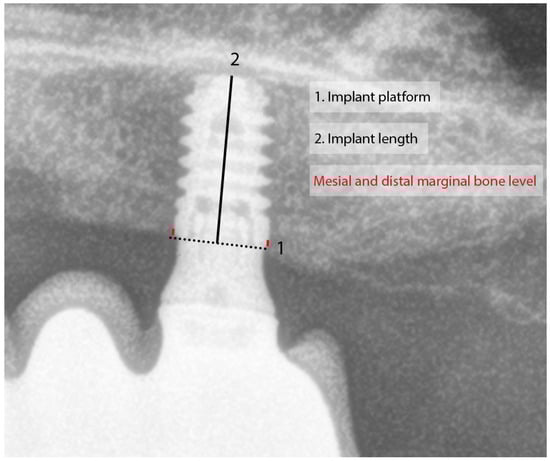

2.2. Statistical Analysis

| Mesial MBL b (mm) (median; range) | loading | 0.0 (−1.6 to 0.3) | 0.0 (−0.71 to 0.0) | 0.088 a |

| Distal MBL b (mm) (median; range) | −0.4 (−2.2 to 0.0) | −0.4 (−0.8 to 0.0) | 0.789 a | |

| Mesial MBL b (mm) (median; range) | Last radiograph | 0.7 (−3.9 to 0.0) | 0.4 (−1.0 to 0.0) | 0.005 a |

| Distal MBL b (mm) (median; range) | −0.8 (−3.2 to 0.4) | −0.7 (−3.1 to 0.0) | 0.155 a | |

| Variation in MBL b–mesial (mm) (median; range) | −0.3 (−3.9 to 0.1) | −0.2 (−1.0 to 0.1) | 0.092 a | |

| Variation in MBL b–distal (mm) (median; range) | −0.4 (−3.2 to 0.8) | −0.2 (−2.8 to 0.32) | 0.196 a | |